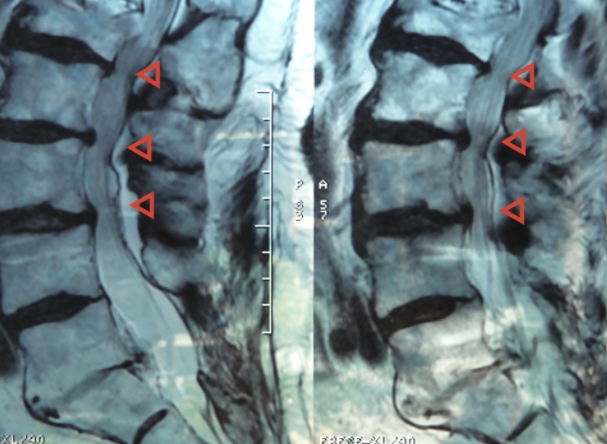

그 허리통증 원인을 특정할 수 있고 많이 알려진 허리 질환인 요추추간판헤르니아가 바로 허리 디스크 입니다. 척추뼈 사이에 있는 추간판이 망가져서 그 안에 있는 젤라틴 같은 디스크가 탈출되어 신경을 압박하면서 통증이 나타납니다.

추간판 이라 불리는 곳은 수분이 많이 함유된 젤리 모양의 수핵과 그것을 둘러싸고 있는 연골조직으로 이루어져 있습니다. 이들은 요추에 가해지는 압력을 분산시켜 충격을 완화해주는 쿠션 역할을 해 주고 있습니다. 그런데 연골조직이 탄력을 잃고 작은 균열이 생기면서 수핵의 일부가 밖으로 탈출하게 됩니다. 그래서 허리 디스크 질환을 추간판 탈출증이라고 합니다.

밖으로 밀려난 수핵이 신경을 압박해서 허리 통증이 생기는데 이 상태를 방치하게 되면 수핵이 점점 더 밖으로 밀려나와 통증과 저리는 증상이 심해집니다. 허리 디스크와 협착증의 차이 중 눈에 보이지는 않지만 발생 원인과 연령대가 다르다는 점이 가장 크다고 할 수 있습니다.

척추는 추골이라 불리는 뼈가 연결되어 이루어져 있습니다. 그런데 나이를 먹으면서 노화와 함께 추골에 있는 척추관이라 불리는 신경이 통과하는 길이 좁아지게 됩니다. 이렇게 좁아지게 되면 그 안을 통과하고 있는 신경이 압박을 받아서 허리통증과 엉덩이, 다리가 저리는 증상 까지도 나타나게 됩니다.

노화 등의 영향으로 추간판이나 요추가 변형 변성되어 척추관이 좁아지면 그 안을 통과하는 마미신경이 압박을 받게 됩니다. 마미신경이란 다리쪽 신경을 조절하는 신경입니다. 그런데 이 부분이 압박을 받으면 신경이 영향을 받아 다리에까지 통증이 나타나고 저리는 등의 척추관 협착증 증상 보이게 됩니다.